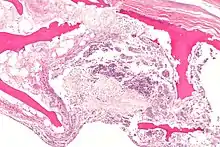

Necrotic bone and inflammation histology slide

The current etiology or origin of this disease is unknown. Some studies theorized that bone remodeling is maintained in a microenvironment in the FH meaning that there is a greater local component to changes to the femoral head than the normal systemic way that bone remodeling is handled throughout the body. As a whole our body goes through bone remodeling using various hormones and glucocorticoids to balance the uptake and output of bone throughout the entire body. The local portion is considered to be controlled partially by inflammatory cells called cytokines and individual growth factors. The theory is that the local bone remodeling is malfunctioning and overpowering the systemic bone remodeling causing the FH to be highly susceptible to necrosis. Studies have determined that there are risk factors that are more than likely associated with the development of the disease but many of them are very broad and include large groups of people for example alcoholics, diabetics, and many other common core morbidities. Unfortunately, most are classified under idiopathic due to being unable to truly narrow down the origin of why it only happens to the head of the femur. What most clinicians observe is that the head of the femur seems to almost have a system of its own somewhat separate from the rest of the femur. There are many theories as to how the head of the femur dies unlike why it is happening.[3]